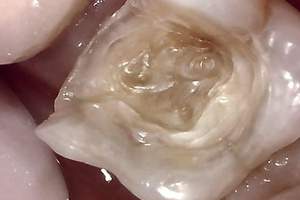

治療中①

治療中①:つめ物をとったところ。茶色い部分は虫歯になっている。